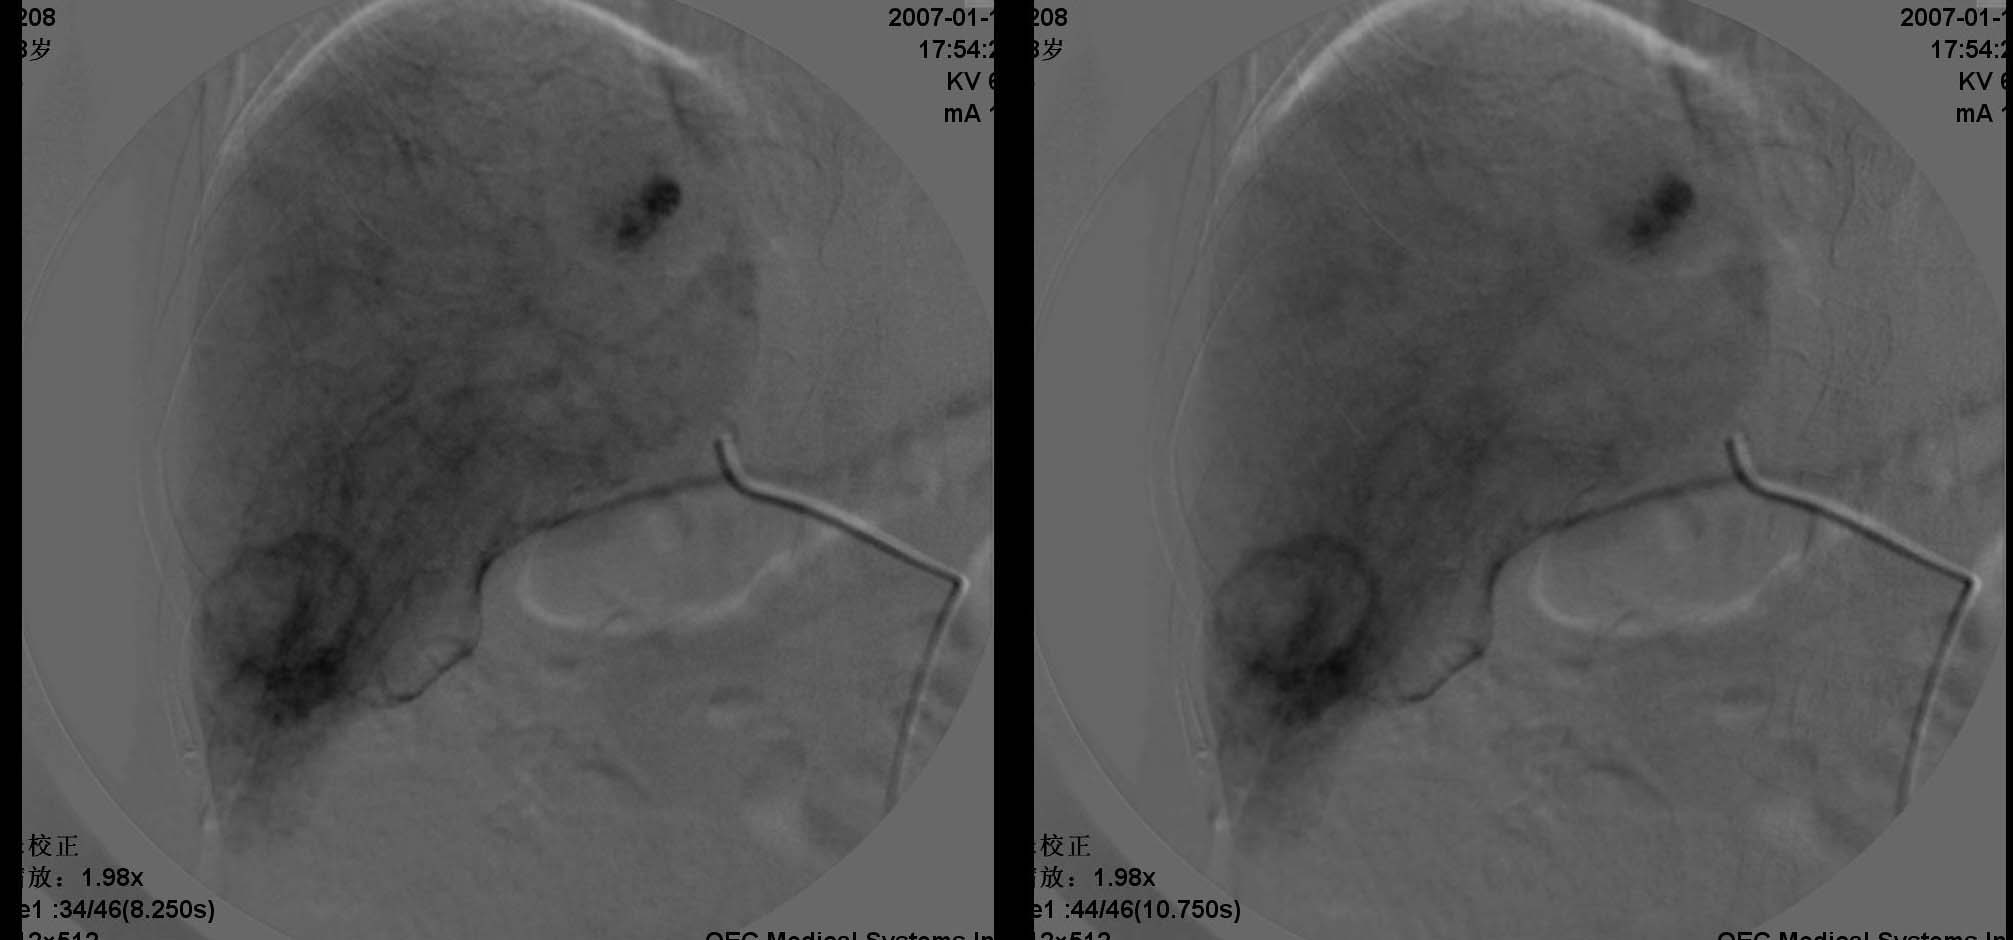

五、血管瘤

血管瘤的dsa诊断与ct诊断同一理论,但通常出现“枝头挂果征”象或“腊梅征象”,征象出现一般见于较大血管瘤,较大血管瘤也可出现动静脉短路(avs),此例血管瘤较小,“枝头挂果征”不明显。

六、脾脏由于ct上低密度病灶很小,dsa并没有显示明确转移性肿瘤的染色区域或低密度区域。

治疗:介入中将微导管亚段选择性进入右肝环状染色区域主干动脉分支,将5-fu750mg、ddp60mg做tai,再将超液态碘化油6ml+mmc20mg +平阳霉素8mg做tae,术中适当调整微导管位置,将碘化油+平阳霉素适量定向飘向血管瘤区域,再将5f rh 导管转向脾门方向,将5-fu250mg、ddp20mg做脾动脉灌注治疗。